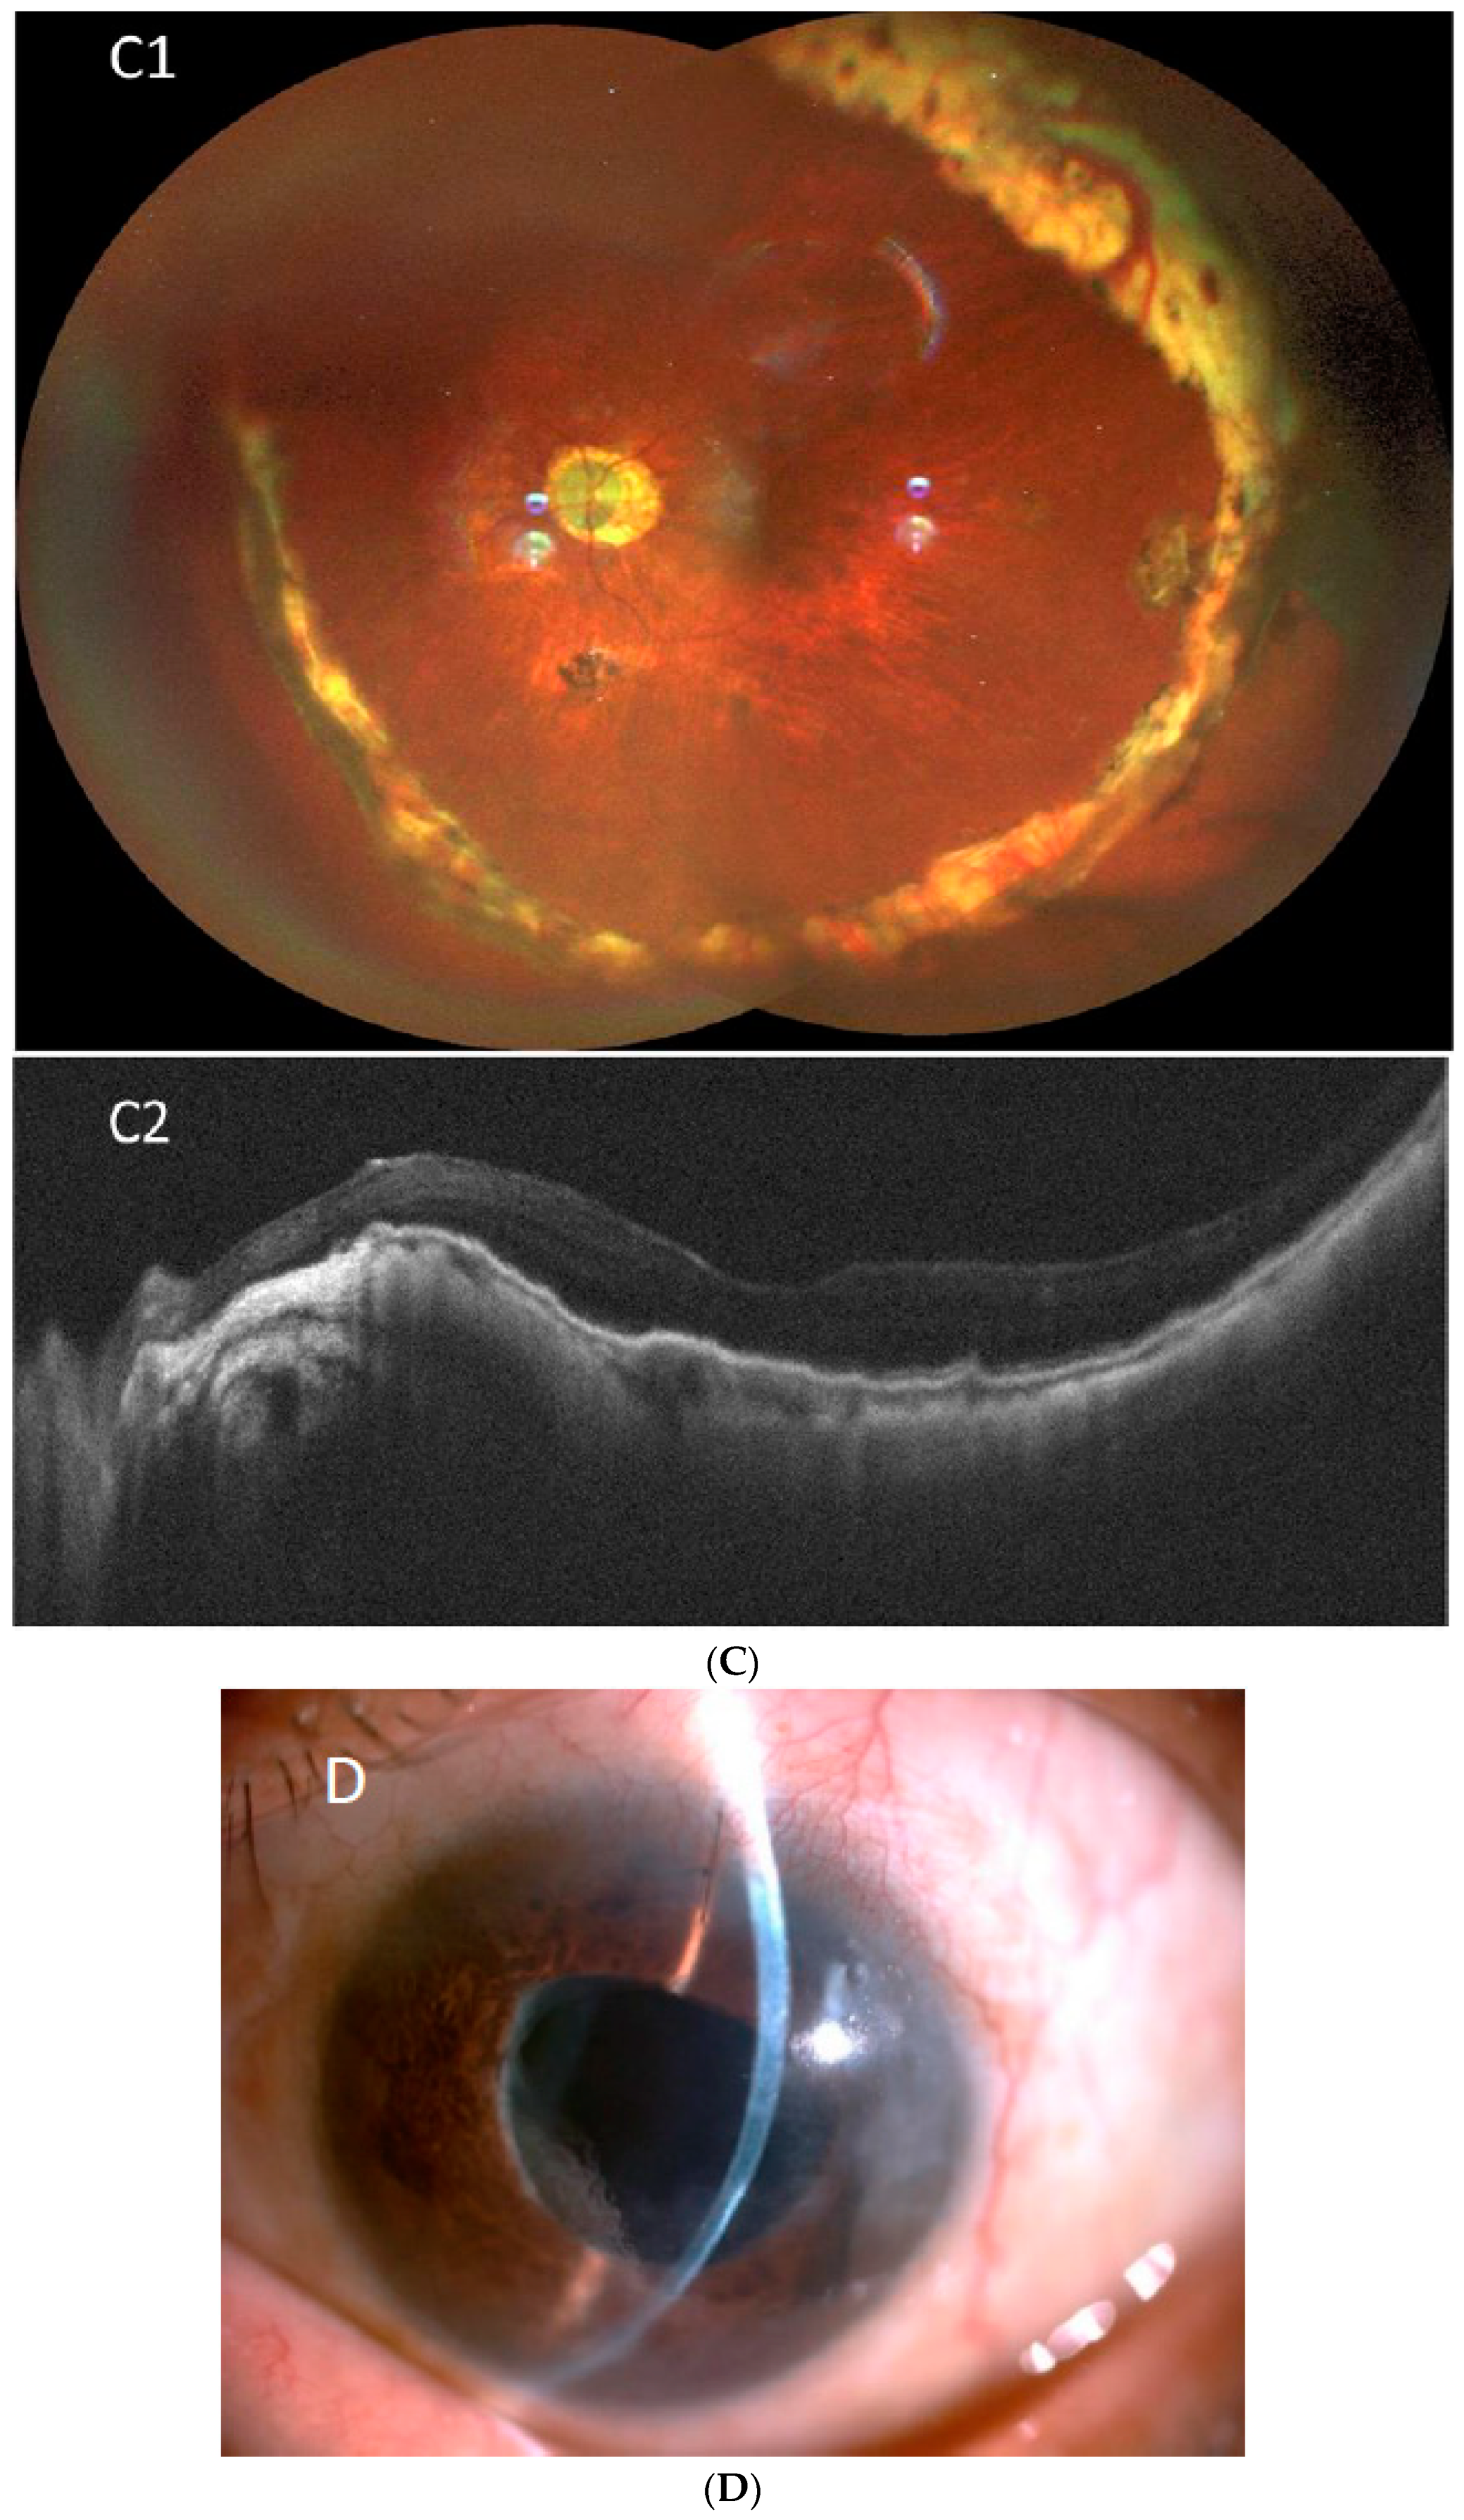

| 6 | 58 | F | S | HM (2.3) | 14 | + | + | + | PPV*2, SO, Lens extraction | PC-IOL | 416 | 270° retinectomy + SO removal + IVIA | 360° pRD | - | 30 | 0.1 (1.0) | WNL | IVIA*2, IVTA*2, mild CO, recurrent VH |

| 7 | 52 | F | R | LP(+) | 5 | + | + | + | SB, PPV for ERM | PC-IOL | 312 | 180° retinectomy + SO + IVIA | 180° pRD | - | 10 | HM (2.3) | 8 | |